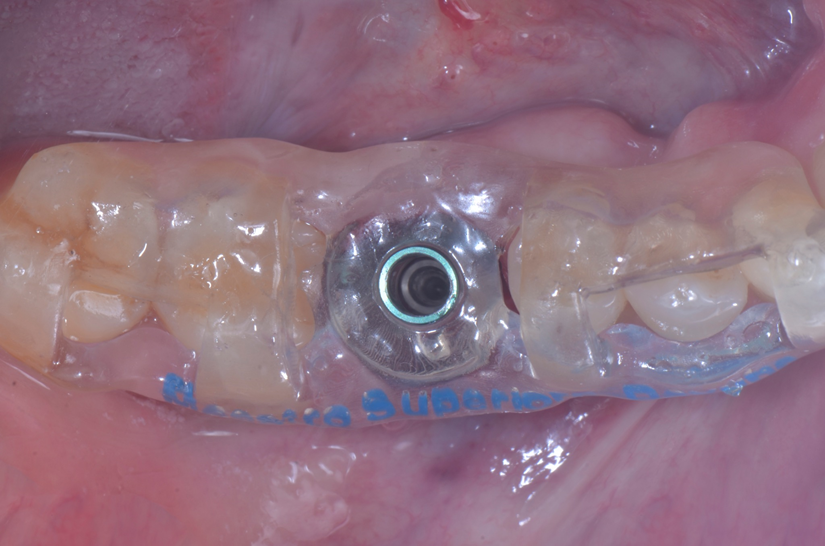

O paciente apresentou fratura vertical mésio-distal no elemento 46. Foi planejada a exodontia minimamente traumática e instalação imediata do implante Maestro Superiore (Implacil Osstem) utilizando uma guia prototipada. Após a exodontia, o implante foi instalado seguindo o protocolo de cirurgia guiada. O GAP vestibular foi preenchido com o Extra Graft. Um cicatrizador personalizado impresso com haletas facilitadoras foi capturado com resina flow e instalado. Após 30 dias, foi realizado escaneamento indireto para obtenção do perfil de emergência, utilizando protocolo digital com sobreposição do cicatrizador escaneado para confecção da coroa definitiva em zircônia policristalina estabilizada por ítria.

O uso de cicatrizadores personalizados, especialmente confeccionados por impressão 3D, tem ganhado destaque por permitir a conformação tecidual progressiva, facilitando a reprodução do perfil de emergência no fluxo digital6,7. A captura do cicatrizador com haletas de retenção com resina flow e seu posterior escaneamento são etapas críticas para assegurar a fidelidade da transferência do perfil de emergência e garantir um planejamento restaurador mais previsível8.